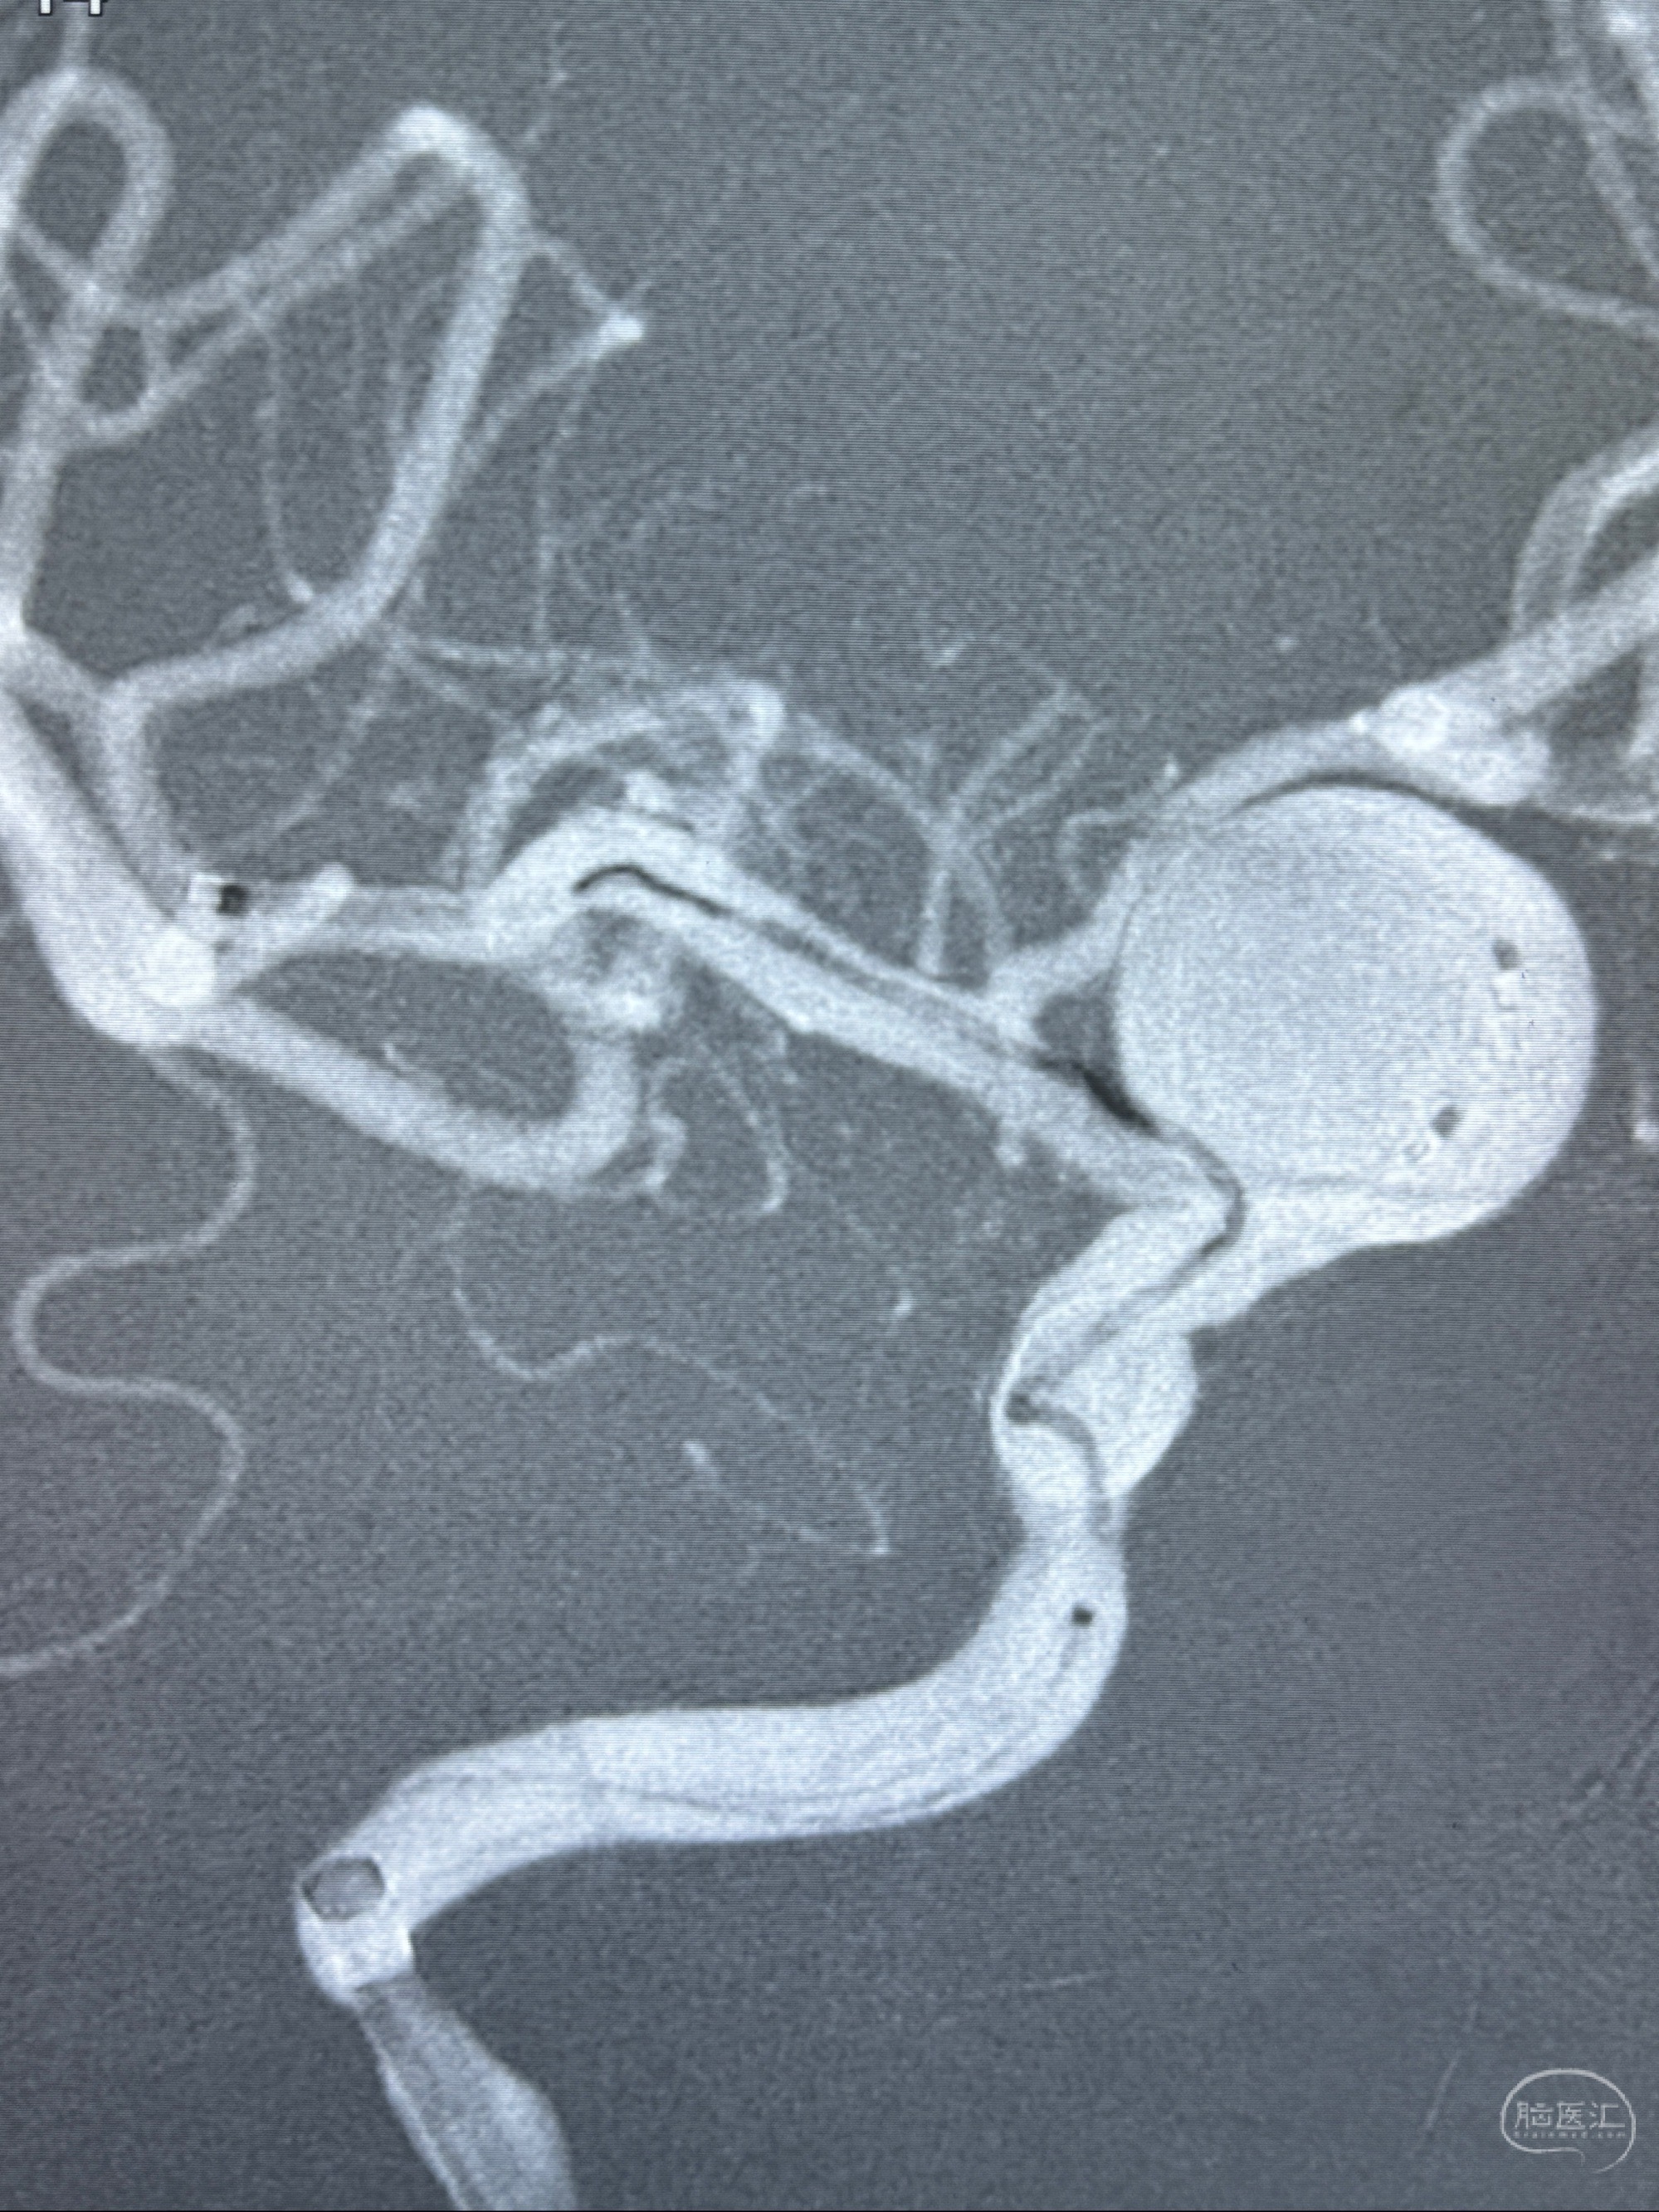

2023-12-27术后第十天复查DSA

支架贴壁佳,但可见射流,咋办?

2024-01-08全麻下再行植入密网支架一枚

Tubridge 4.5-35mm

支架植入顺利,贴壁佳,支架内血流通畅,动脉瘤内血液滞留明显